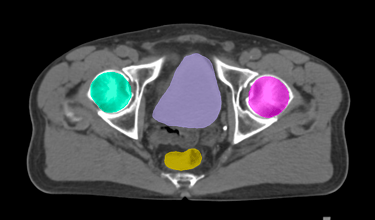

The DAM Contour features a comprehensive collection of OARs and CTVs that are ready for immediate use, without the need for manual creation of atlases or manual adjustment of data. This product includes all standard OAR and CTV structures (over 117 in total).

The Pelvis lymph node region encompasses lymph nodes that include the obturator lymph nodes, internal and external iliac lymph nodes (limited anteriorly at the level of the femoral heads), and extends up to the common iliac lymph nodes, covering the L5/S1 region.

Pelvis